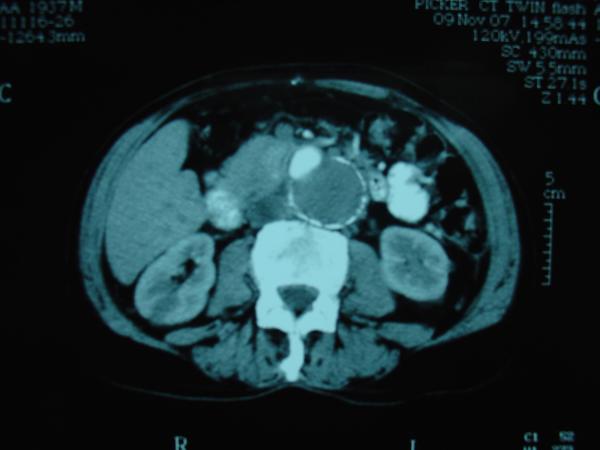

Endovascular repair of anastomotic abdominal aortic aneurysm, after aortobifemoral bypass

Vascular Clinic, Naval and Veterans Hospital of Athens

AVEM2009-Thessaloniki